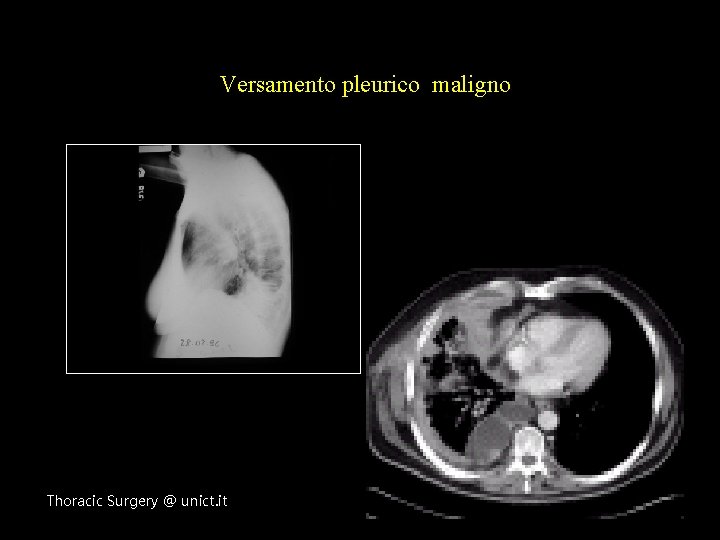

Versamento pleurico maligno Thoracic Surgery @ unict. it